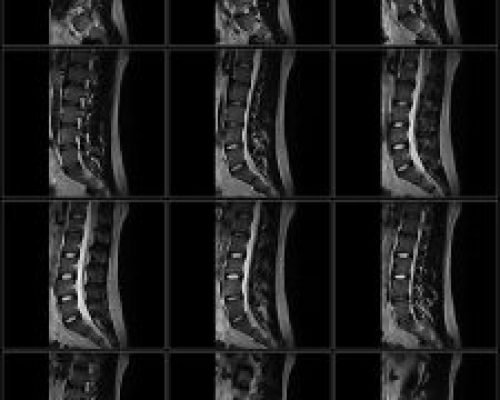

The PICA MRI system is our flagship product with its unique open architecture, advanced hardware platform and leading-edge clinical applications make it ideally suited for patient comfort, fast acquisition times and excellent image quality. The PICA has passed all ACR Accreditation requirements of 4 MRI modules: Head, Spine, Body and MSK. This accreditation also means that patient scans from PICA is approved for financial reimbursement by the US Government MEDICARE program as well as private insurance companies in the US.